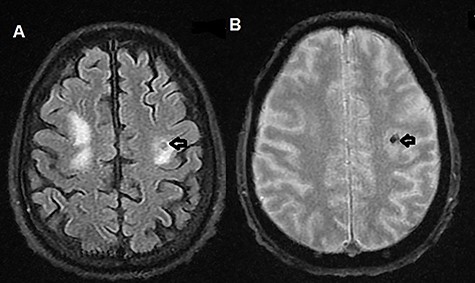

The patient was admitted to the hospital. Brain magnetic resonance imaging (MRI) revealed multiple multifocal hemorrhagic lesions with surrounding edema involving the cerebellum and both cerebral hemispheres, consistent with hemorrhagic metastatic lesions (Figs 1A, B and 2A, B).

(A) T2-weighted MRI axial image showing right parietal isointense lesion with extensive surrounding edema (black arrow); (B) T2-weighted MRI axial gradient echo sequence showing left parietal lesion compatible with hemorrhagic foci (black arrow).